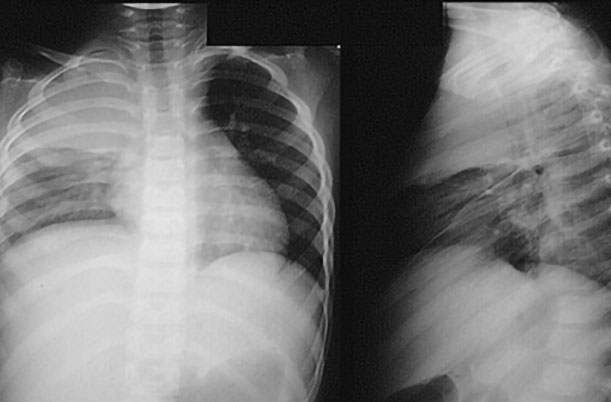

viem-phoi-co-sot-khong-1 Viêm phổi có sốt không? - Vấn đề được nhiều người quan tâm

viem-phoi-co-sot-khong-2 Viêm phổi có sốt không? - Sốt không phải dấu hiệu chính để xác định bệnh